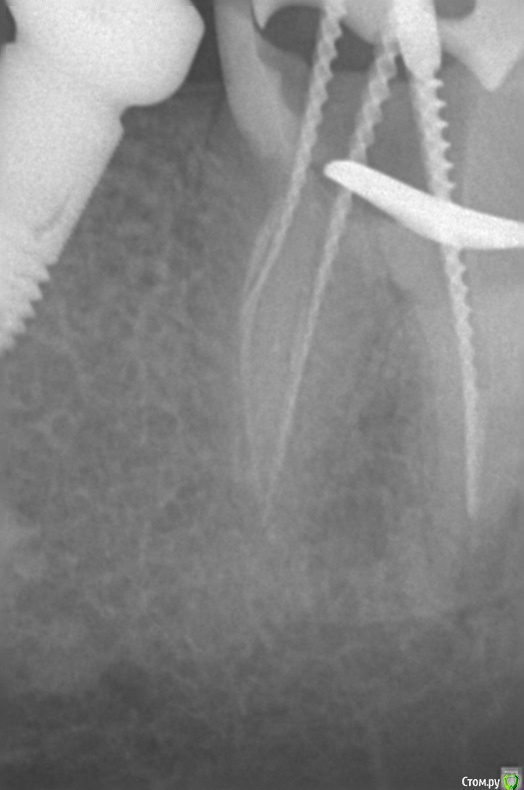

Dmitriy_ Опубликовано 2 февраля, 2017 Поделиться Опубликовано 2 февраля, 2017 Доброго дня уважаемые врачи! Протезируете или удаляете такие зубы?Так получилось что лечение (клиника1) и протезирование+имплантация (клиника2) делаю в разных местах, произошла некоторая несогласованность действий. Коронка в проблемном месте ниже уровня десны, до кости в одном месте доходит. Хирургическое удлинение коронки в клинике2 делать отказались из-за рядом стоящего импланта, т.е. этот вариант как я понял не обсуждается. Но протезировать могут, спросил можно ли добиться герметичности, ответ положительный, сложно но можно. Но прогноз сделать сложно. Мне не хотелось бы возвращаться к этому вопросу года через 3, плюс лечение не дешевое. Спасибо! Ссылка на комментарий

Доктор Добрых Дел Опубликовано 3 февраля, 2017 Поделиться Опубликовано 3 февраля, 2017 Однозначно удаление и имплантация. И дело не в герметичности прилегания будущей коронки а в том что в том месте под десной где будет искусственная коронка должны быть ткани зуба к которым прикрепляется десна. Так как там будет инородное тело, то прикрепления десны не будет. Будет хроническое воспаление, которое приведёт к развитию зубодесневого кармана, кариесу корня и в конечном счёте к удалению зуба (из-за убыли кости может пострадать и рядом стоящий имплантат). Ссылка на комментарий